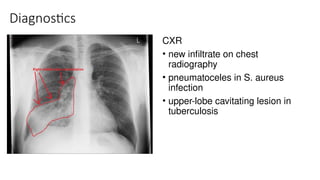

Diagnostics

CXR

• new infiltrate on chest

radiography

• pneumatoceles in S. aureus

infection

• upper-lobe cavitating lesion in

tuberculosis